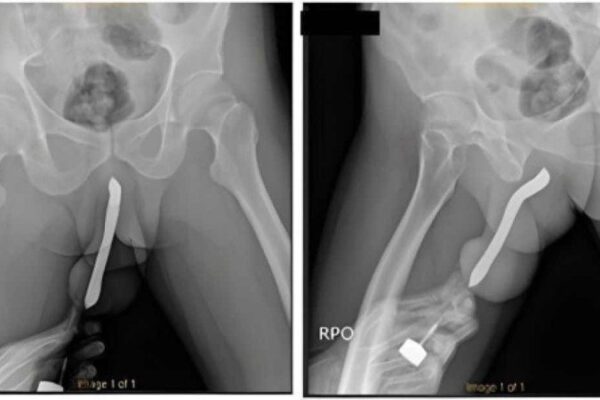

Um influenciador fitne compartilhou ua experiência apó pa ar ei hora em uma me a de cirurgia apó um "exame de rotina" De acordo com Joey Swoll, durante o procedimento de angiograma...